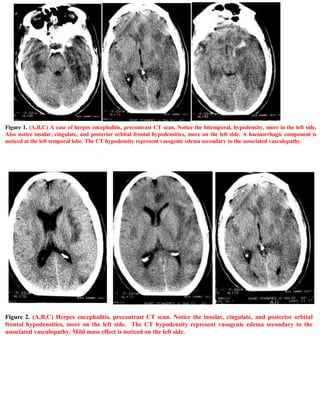

Figure 2. (A,B,C) Herpes encephalitis, precontrast CT scan. Notice the insular, cingulate, and posterior orbital

frontal hypodensities, more on the left side. The CT hypodensity represent vasogenic edema secondary to the

associated vasculopathy. Mild mass effect is noticed on the left side.